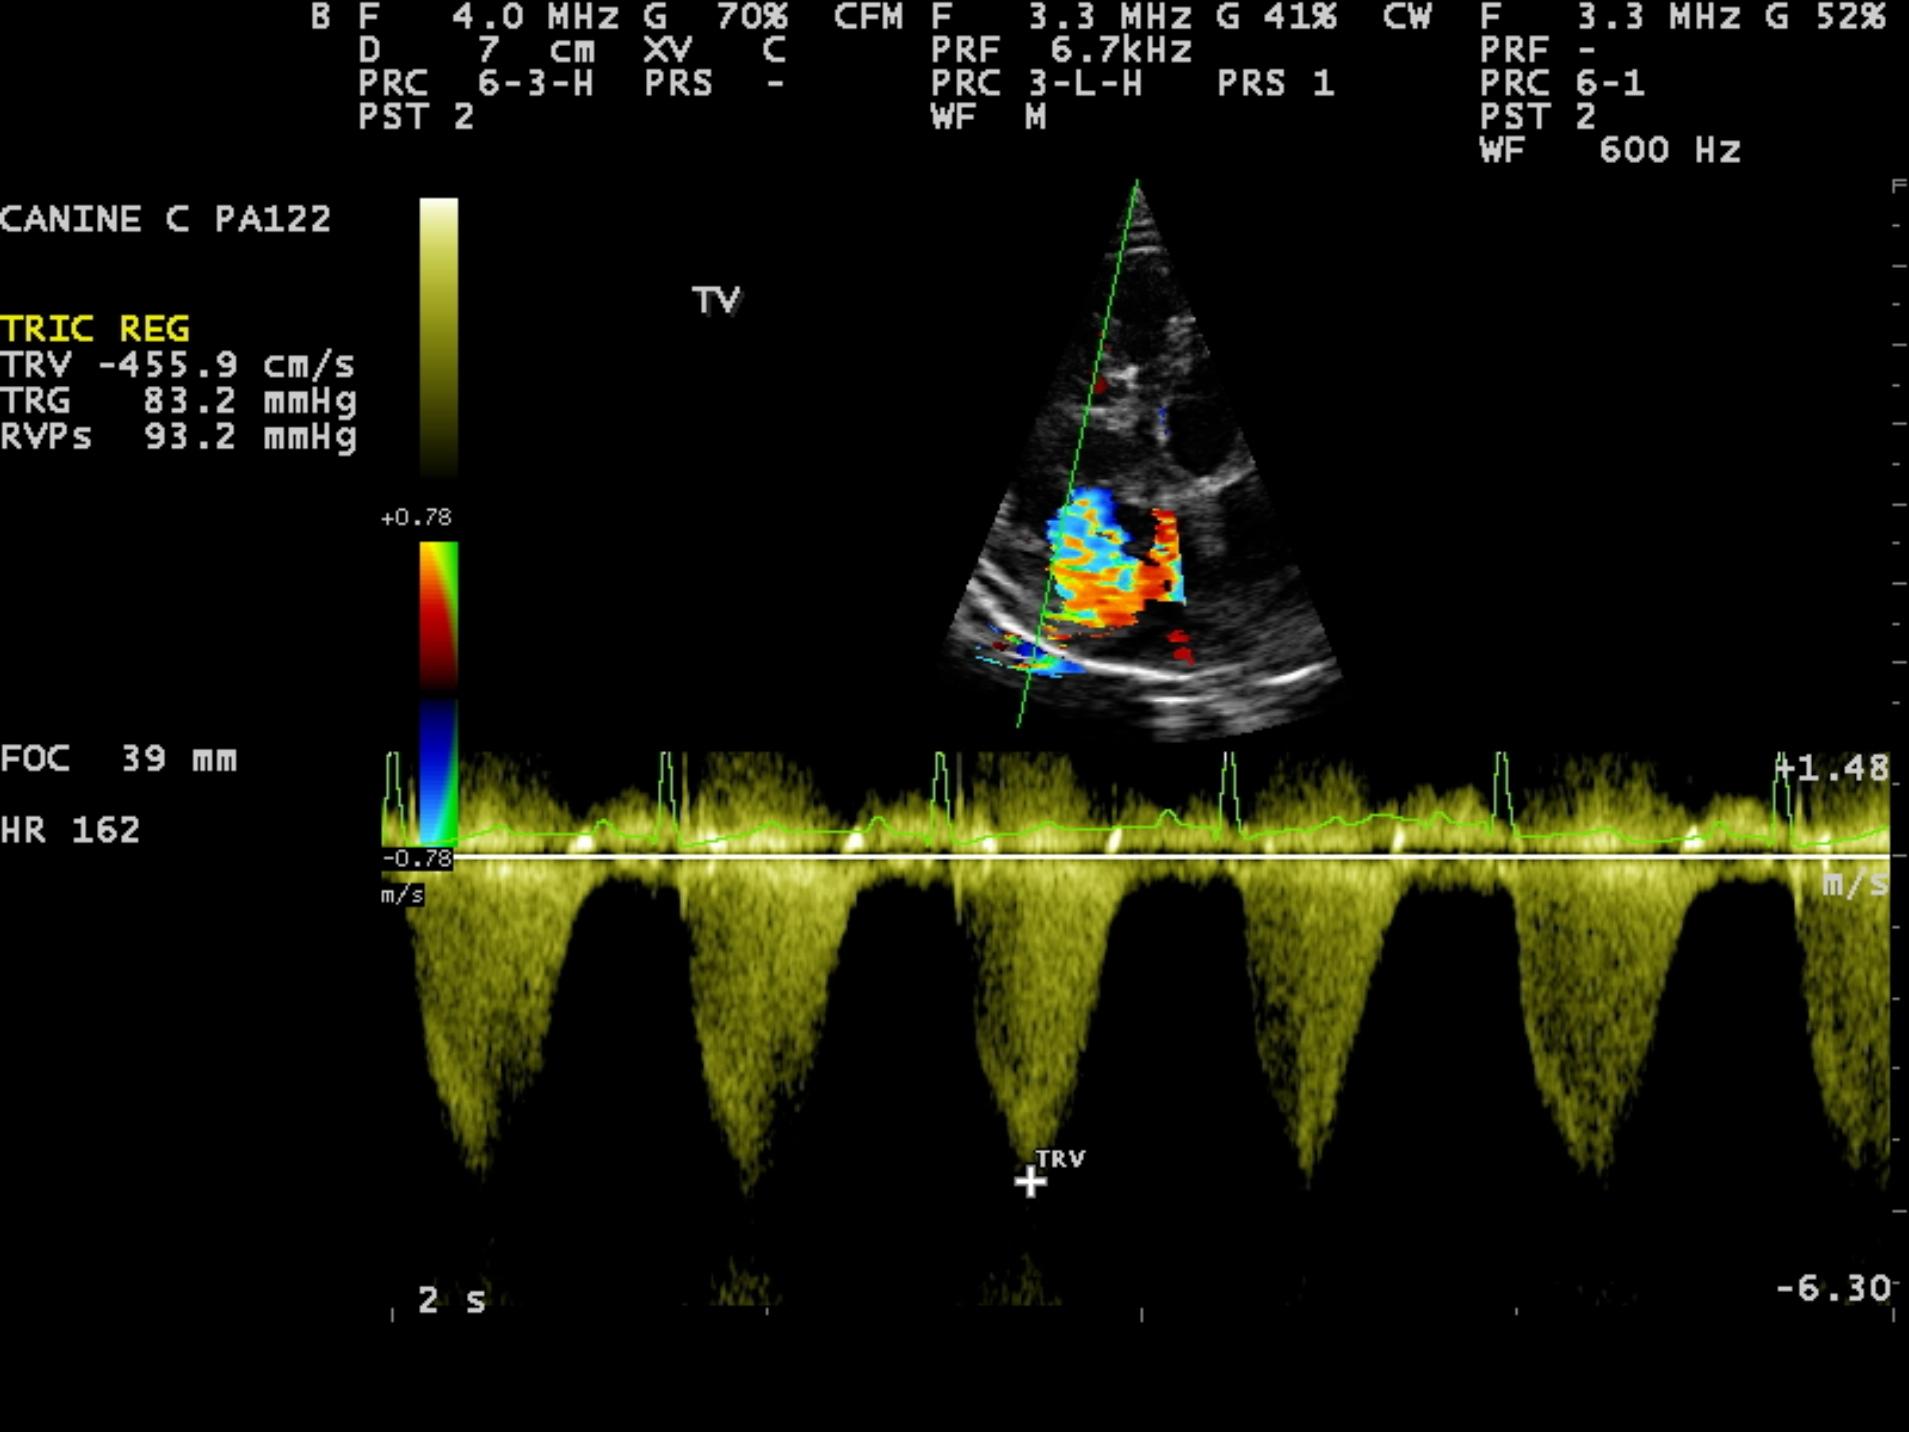

An 8-year-old F Maltese was presented for examination. A grade 5/6 systolic heart murmur was noted. Radiographs revealed severe generalized cardiomegaly and an unremarkable pulmonary parenchyma. Moderate hepatomegaly and ascites was additionally noted.